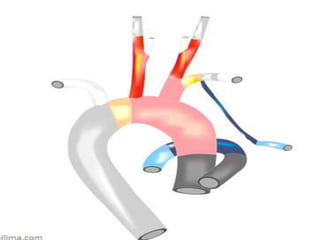

Double aortic arch

A double aortic arch is the most common complete vascular ring that causes

In patients with double aortic arch, the ascending aorta arises normally, but as it

leaves the pericardium it divides into two branches, a left and a right aortic arch that

join posteriorly to form the descending aorta.

The left arch passes anteriorly and to the left of the trachea in the usual position and

is joined by the ductus arteriosus (or more often a ligamentum arteriosum), where it

becomes the descending aorta.

The right aortic arch passes to the right and then posterior to the esophagus to join

the left-sided descending aorta, thus completing the vascular ring .